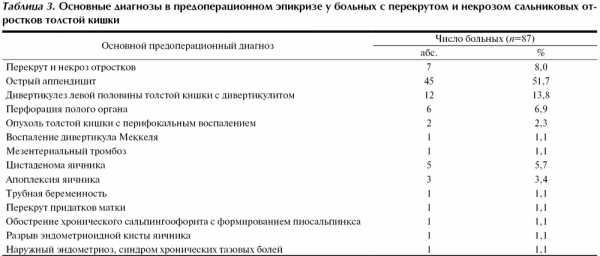

Перекрут и некроз отростков по результатам обследования до операции был заподозрен у 30 (34,5%) больных. У 7 (8,0%) из них он был основным диагнозом в предоперационном эпикризе, у 25 (27,5%) подозревался при проведении дифференциальной диагностики с другими острыми хирургическими и гинекологическими заболеваниями. У остальных 57 (65,5%) больных показанием к оперативному вмешательству послужили подозрение на другие острые хирургические и гинекологические заболевания органов брюшной полости и необходимость дифференциальной диагностики между ними. Основные диагнозы в предоперационном эпикризе, по поводу которых выполнялось лапароскопическое вмешательство, представлены в табл. 3.

Наиболее частыми предоперационными диагнозами были острый аппендицит (51,7%), дивертикулез с дивертикулитом (13,8%), перфорация полого органа (6,9%), цистаденома яичника (5,7%), апоплексия яичника (3,4%). Стоит отметить, что трудности диагностики перекрута и некроза отростков приводили к тому, что у большинства больных — 60 (68,9%) — лапароскопическое вмешательство проводилось с целью дифференциальной диагностики между несколькими хирургическими — 52 (59,7%), хирургическими и гинекологическими — 6 (6,9%) и несколькими гинекологическими — 2 (2,3%) заболеваниями органов брюшной полости. У 58 (66,7%) больных дифференциальная диагностика проводилась между двумя заболеваниями. У одного больного проводилась дифференциальная диагностика между тремя заболеваниями (острым аппендицитом, острым мезаденитом и перекрутом и некрозом отростка), у одного больного — между четырьмя заболеваниями (дивертикулезом левой половины толстой кишки с дивертикулитом, опухолью толстой кишки с перифокальным воспалением, перекрутом и некрозом отростка и сигмоидитом). Лишь у 27 (31,1%) больных лапароскопическое вмешательство было предпринято в связи с подозрением на наличие какого-либо одного заболевания.